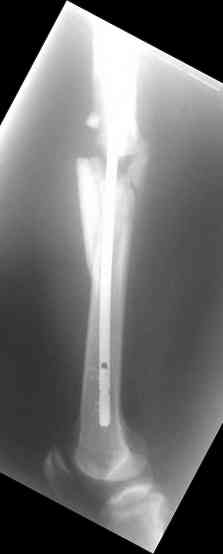

молодй человек 26лет получил С3-перелом правого бедра и легкую черепно мозговую травму (сотрясение головного мозга). Через неделю (противошоковые мереприятия и скелетное вытяжение выполнялось в ЦРБ)оперирован: БИОС бедра стержнем СнМ, Польша. Выписан со швами на амбулаторное лечение по месту жительства в г. Ижевск.Через 1месяц главным врачом больницы, со слов пациента, предложен реостеосинтез пластиной "соберем кость".

Надеюсь сейчас показать перелом, а потом синтез.

Про "кролика", конечно, не очень хорошо с точки зрения деонтологии. Но коллега, Вы думаете кто-нибудь из заядлых Nailer- ов оценит положительно этот остеосинтез? Возможно, на то были объективные причины: отсутствие штифтов большего диаметра..., штифтов, позволяющих блокировать более толстыми винтами..? А уж Plater-ы, конечено засмеют.

У данного пациента есть все основания ожидать несращения. Менять штифт (безусловно тонкий и недостаточно стабильный для этого перелома) на пластину не лучший вариант, особенно, если предполагается открытая операция. Или главный врач в Ижевске имеет ввиду длинную мостовидную пластину LCP по технике MIPO? Тогда шансов на сращение будет больше, чем сейчас, но с нагрузкой придется очень и очень подождать.

Мы бы сейчас перештифтовали : удалить, рассверлить, и забить штифт 13-16 мм диаметром и на пару см. подлиннее. Предпочтительнее штифт, имеющий изгиб во фронтальной плоскости в проксимальном отделе для введения через верхушку б\вертела и имеюший возможность проксимального блокирования по оси шейки бедра.

Не вижу больших оснований для пессимизма, тут все шансы на сращение есть - сделано закрыто, винтики в гвозде есть. С нагрузкой на ногу торопиться не надо только.